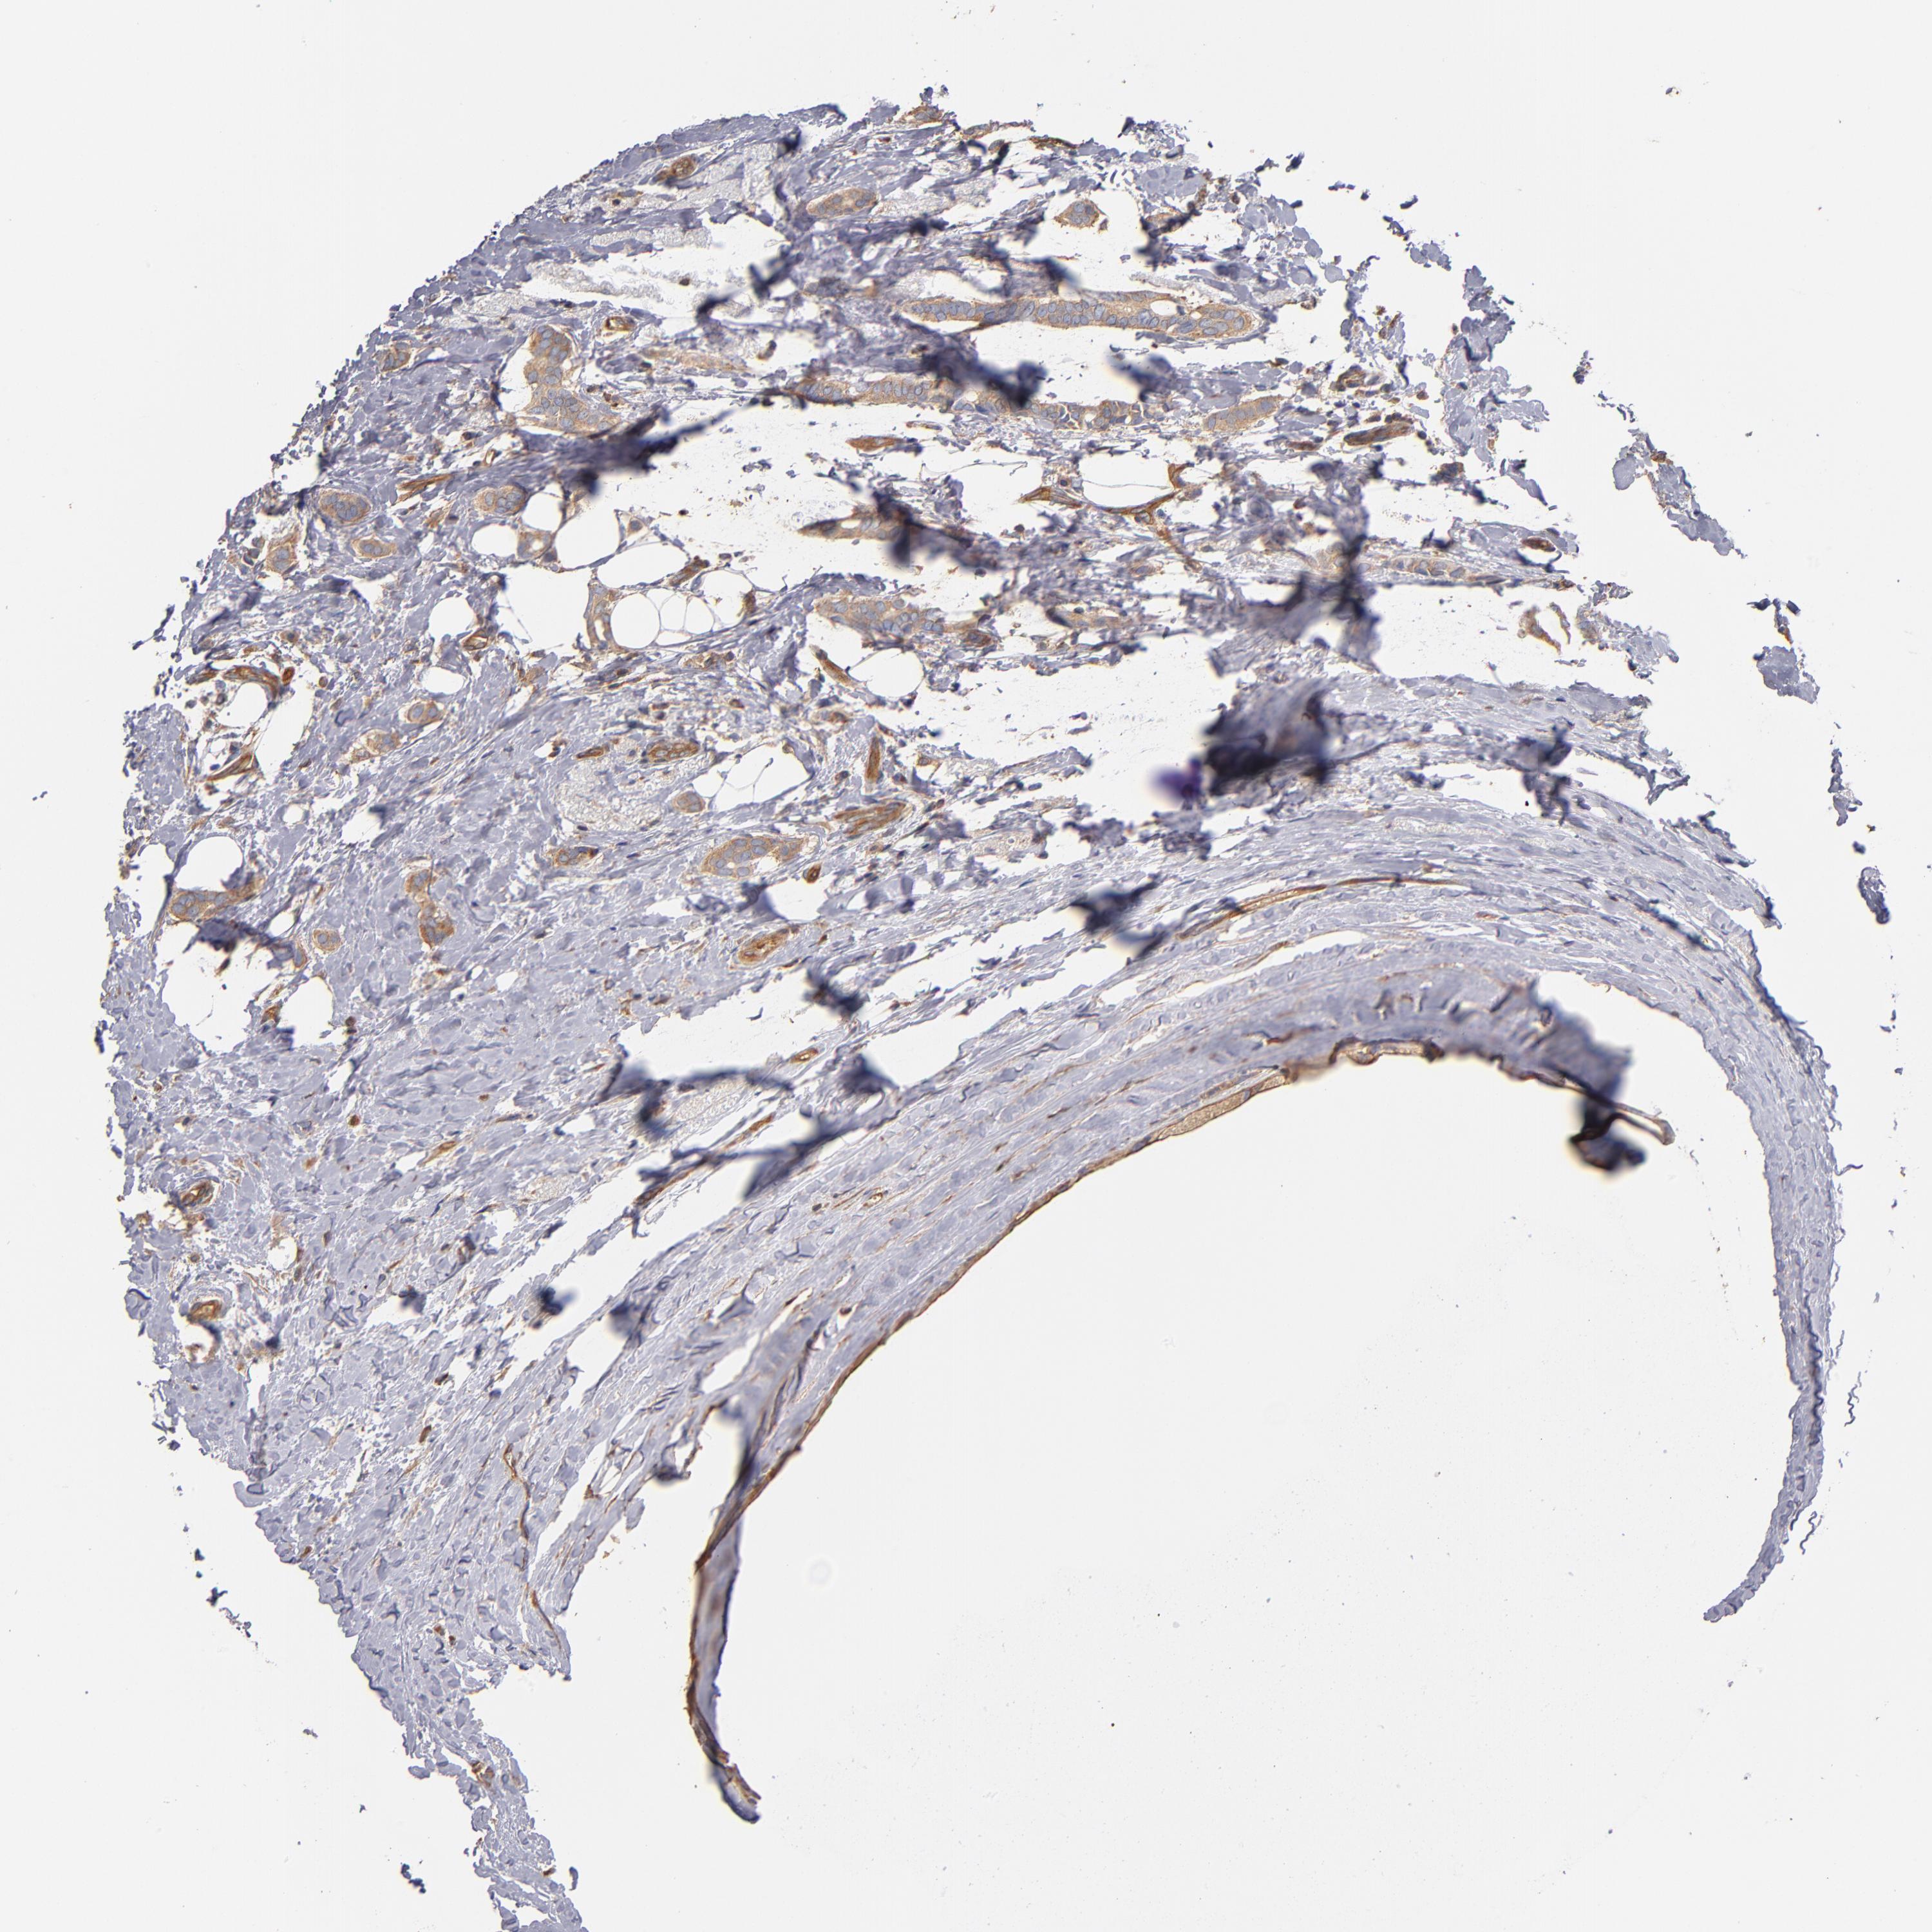

BRCA TCGA BRCA VALIDATION PROTEIN EXPRESSION

ANTIBODIES

AND

VALIDATION